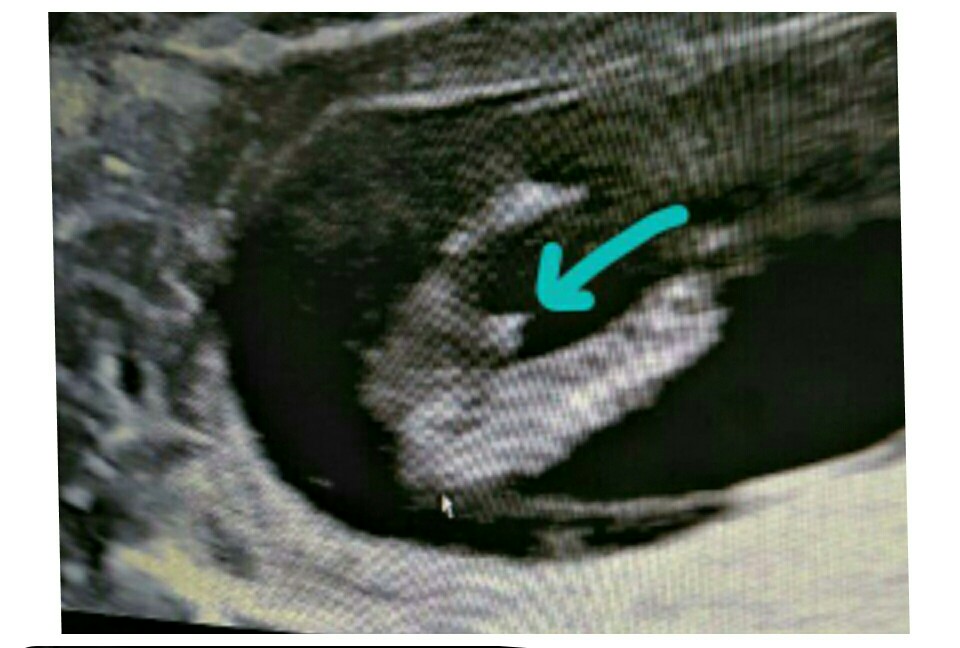

ช่วยดูให้หน่อยค่ะ หมอบอกน่าจะชายแต่คนอื่นๆที่ดูบอกหญิง🤣🤣